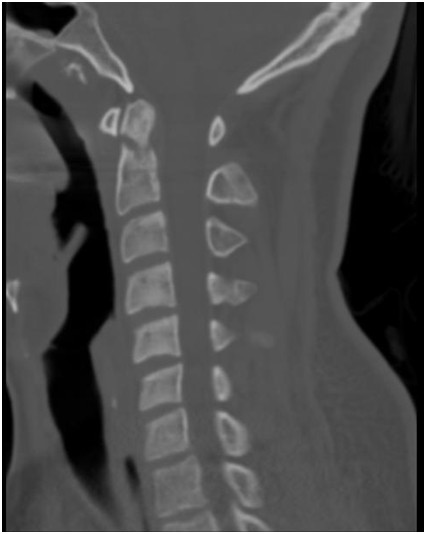

Wskaż prawdziwe stwierdzenia dotyczące patologii widocznej na poniższym skanie w płaszczyźnie strzałkowej z tomografii komputerowej:

1) jest wadą wrodzoną przejścia czaszkowo-szyjnego;

2) jest typem trzecim złamania zęba obrotnika według Andersona i D’Alonzo;

3) jest obarczona istotnym ryzykiem braku zrostu;

4) występuje u osób starszych w wyniku urazu o małej energii;

5) nie wymaga leczenia;

Prawidłowa odpowiedź to: